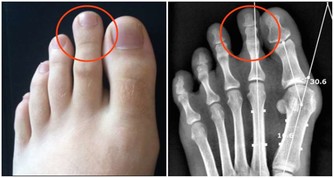

(四)下肢青筋

1.漆部青筋提示漆關節腫大,風濕關節炎。

2.小腿有青筋靜脈曲張嚴重者往往發生腰腿疾病,風濕關節痛。特別多見於久站的老師,久行的農民或喜歡走熱時沖涼的人士。因為寒則入骨傷筋,這是許多人日常生活中不夠注意的問題,最後久積成疾,甚至影響高血壓很難下降。